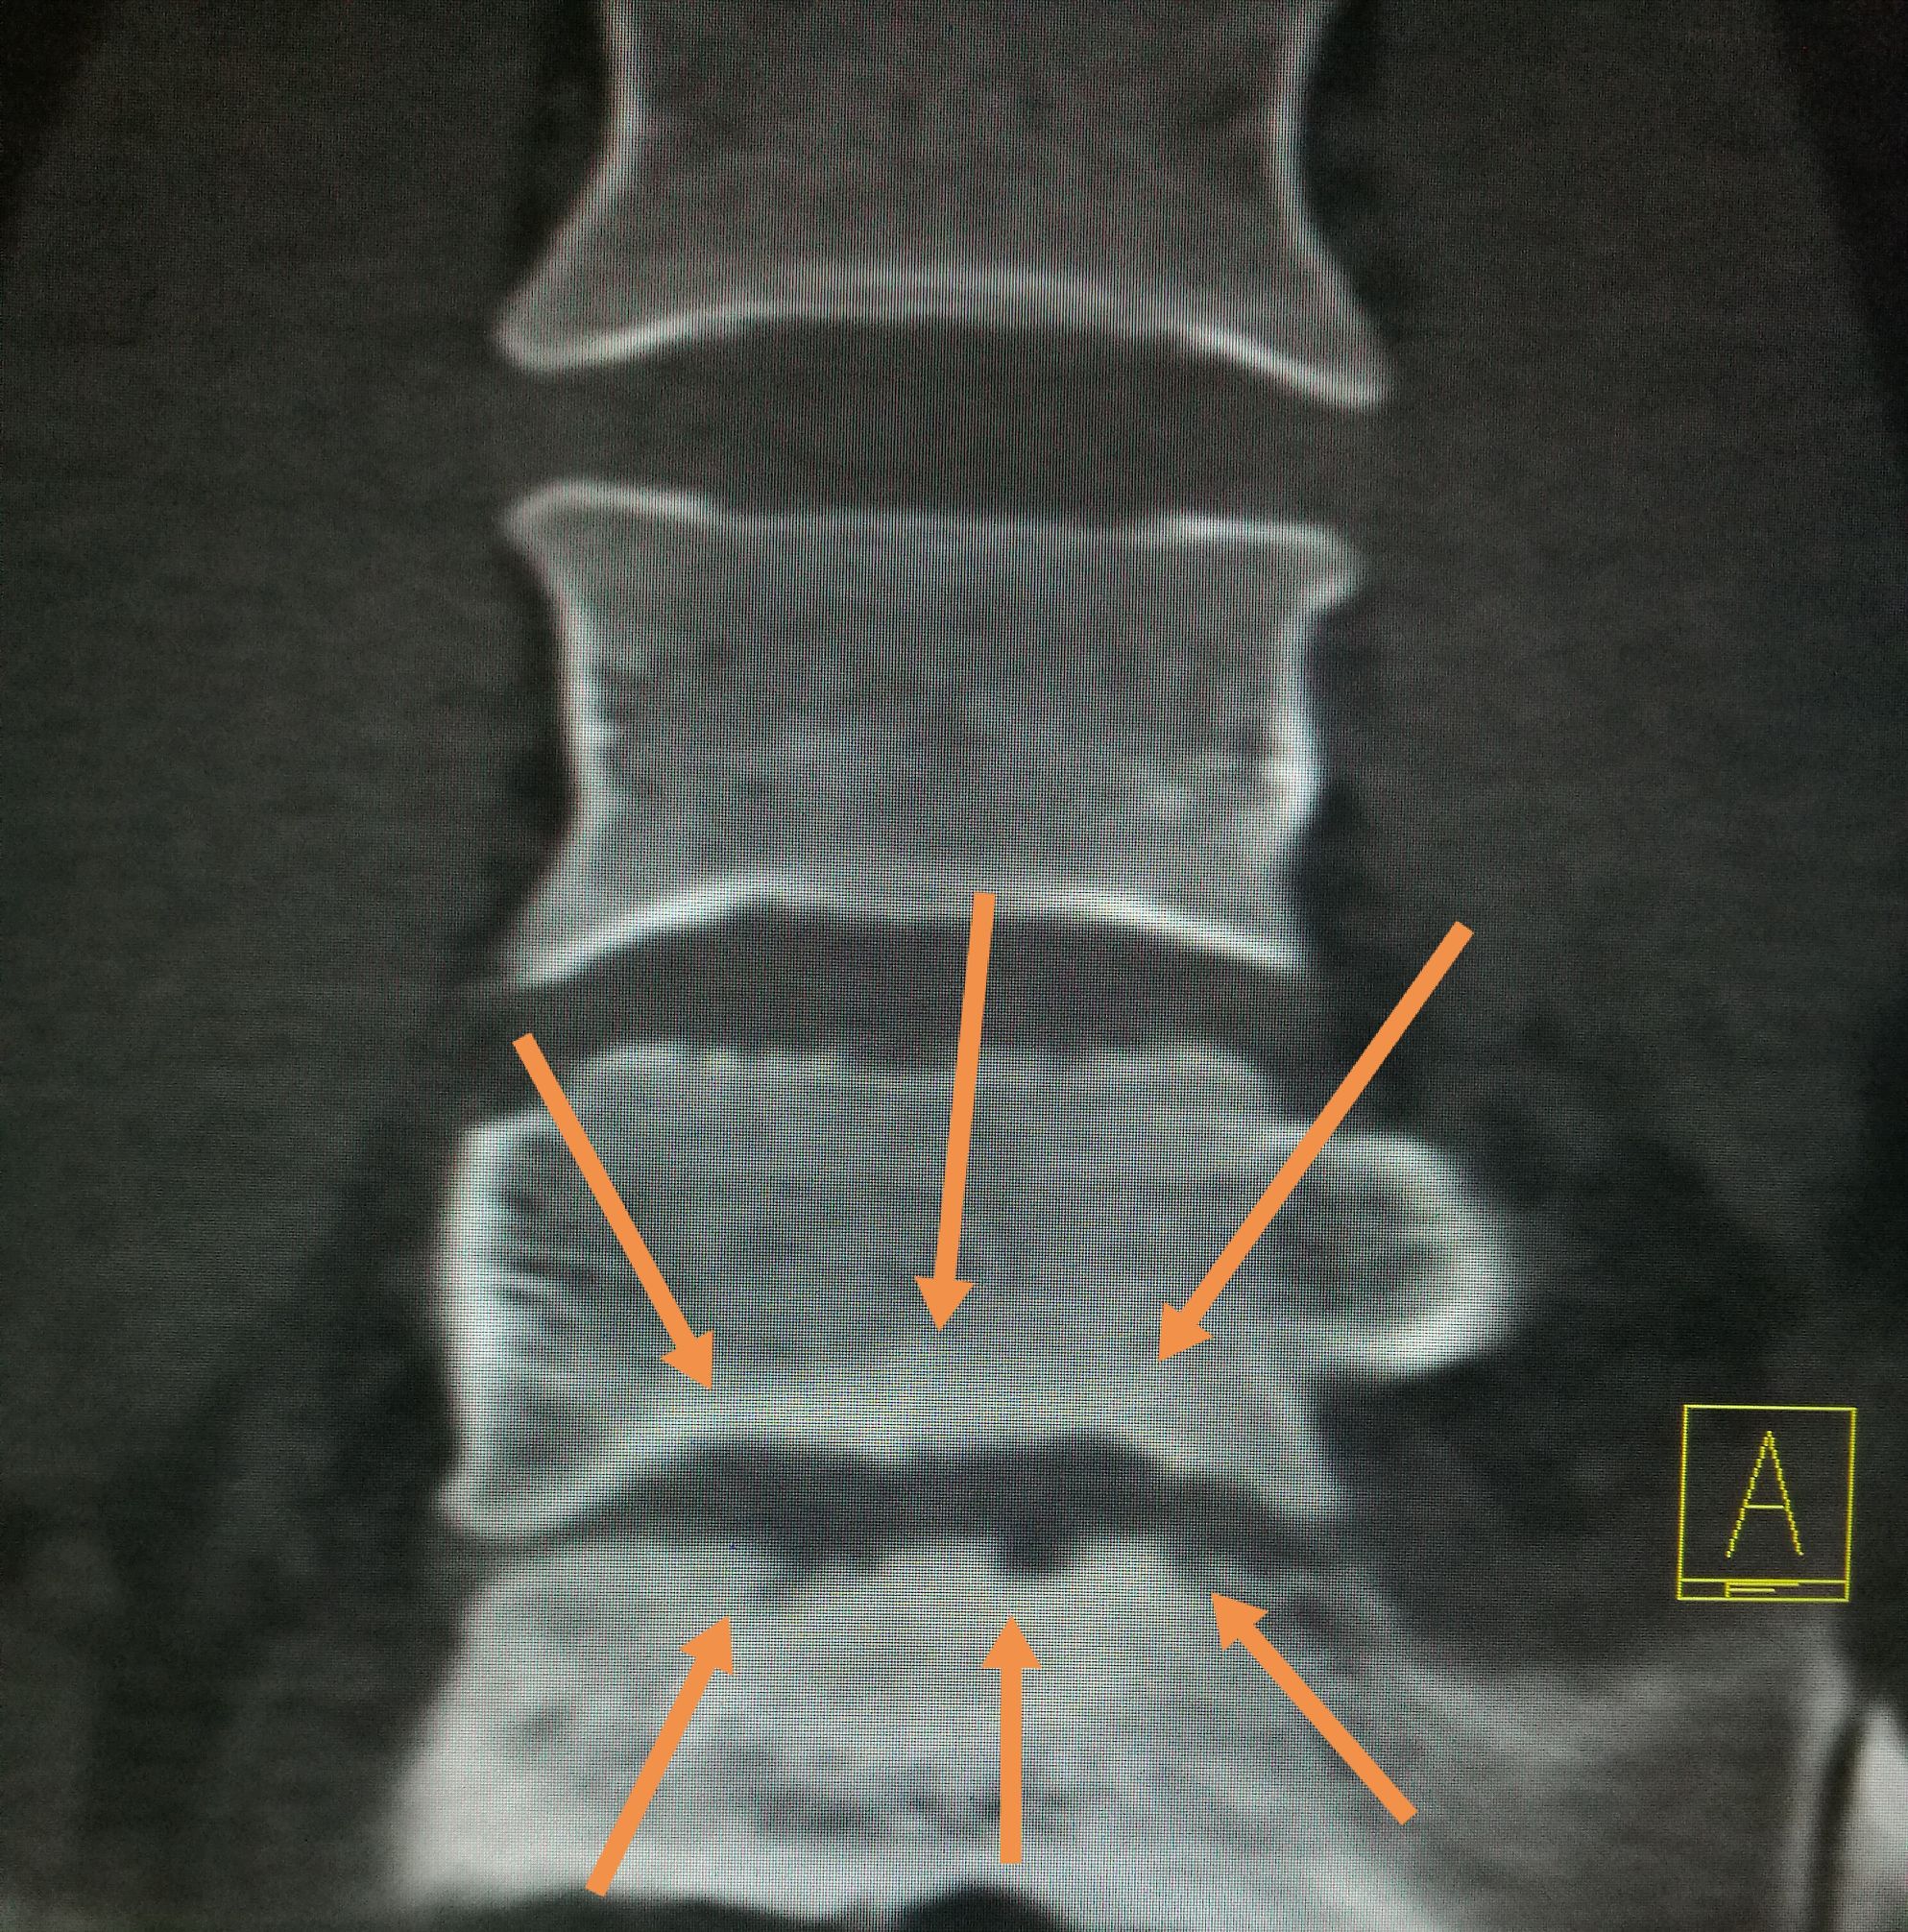

常吃牛羊肉,出现腰背痛,小心☞布鲁氏病 ​​​患者,男,22岁,以腰疼数月前来我处就诊,CT扫描可见第五腰椎下缘,骶椎上缘骨质破坏,骨密度增高,椎间隙未见明显狭窄,椎体旁未见软策划肿胀,未见异常包块,随后追问病史,主诉在*疆新**生活两年,后腰疼,在省防疫站查出来是布鲁氏杆菌感染,今来我处复查。